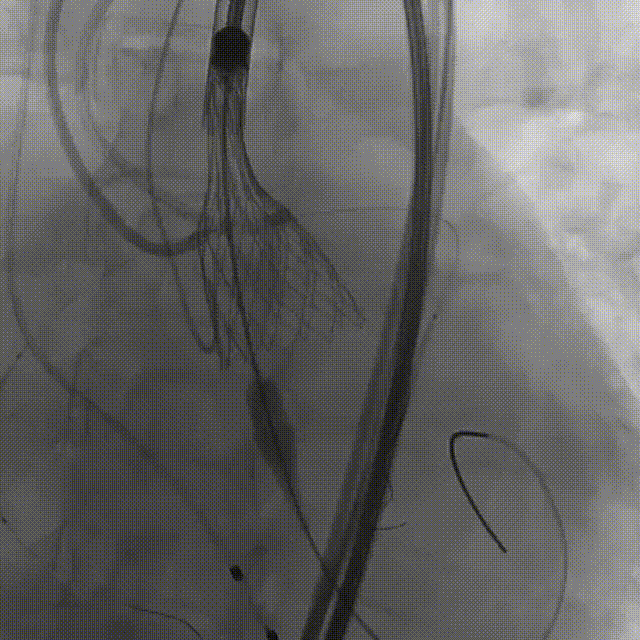

10.右冠行烟囱支架技术

11.左冠造影评估灌注正常,

撤出支架

12.术后造影

术前压差103mmHg

术后压差2mmHg

术后超声评估

术后一周复查超声平均压差是11mmHg,无瓣周漏,瓣膜正常工作。